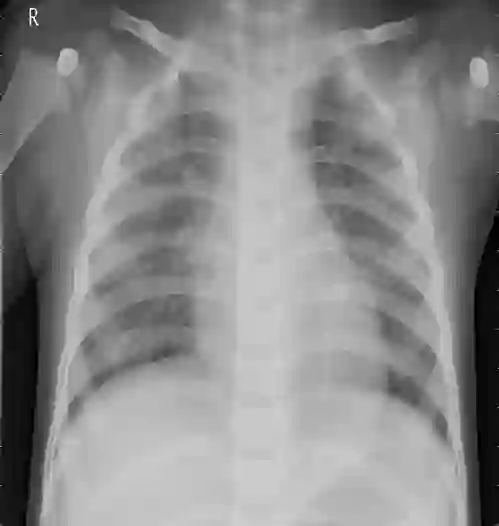

Pneumonia remains a leading cause of morbidity and mortality worldwide. Chest X-ray (CXR) imaging is a fundamental diagnostic tool, but traditional analysis relies on time-intensive expert evaluation. Recently, deep learning has shown immense potential for automating pneumonia detection from CXRs. This paper explores applying neural networks to improve CXR-based pneumonia diagnosis. We developed a novel model fusing Convolution Neural networks (CNN) and Vision Transformer networks via model-level ensembling. Our fusion architecture combines a ResNet34 variant and a Multi-Axis Vision Transformer small model. Both base models are initialized with ImageNet pre-trained weights. The output layers are removed, and features are combined using a flattening layer before final classification. Experiments used the Kaggle pediatric pneumonia dataset containing 1,341 normal and 3,875 pneumonia CXR images. We compared our model against standalone ResNet34, Vision Transformer, and Swin Transformer Tiny baseline models using identical training procedures. Extensive data augmentation, Adam optimization, learning rate warmup, and decay were employed. The fusion model achieved a state-of-the-art accuracy of 94.87%, surpassing the baselines. We also attained excellent sensitivity, specificity, kappa score, and positive predictive value. Confusion matrix analysis confirms fewer misclassifications. The ResNet34 and Vision Transformer combination enables jointly learning robust features from CNNs and Transformer paradigms. This model-level ensemble technique effectively integrates their complementary strengths for enhanced pneumonia classification.